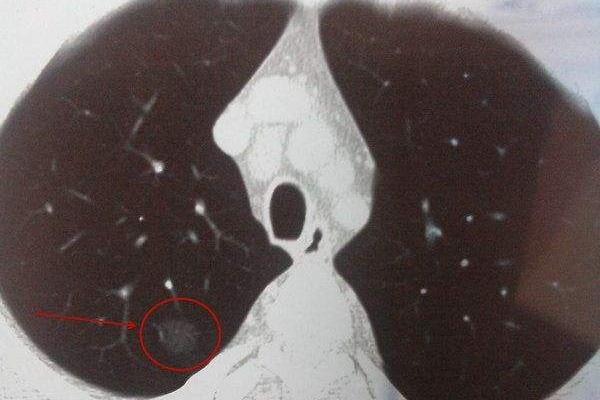

肺是人体呼吸系统重要的组成部分 , 负责帮助人体交换气体 , 维持人体正常运转 。 很多朋友在体检的时候 , 会发现检查结果显示 , 肺部出现了结节 , 这是怎么回事?人体出现肺部结节 , 会有哪些症状?不妨一起来了解一下 。

一般来来说肺部结节在早期是没有明显症状的 , 随着结节的生长 , 人体可能会出现咳嗽、痰多、胸闷、发热等症状 。 根据临床数据显示 , 部分患者可能还会出现支气管扩张等情况 , 对于人体健康影响是非常大的 , 那么哪些人容易出现肺部结节呢?

肺部结节小于这个值 , 通常是良性!

一般来说肺部结节小于5mm恶变的概率非常低 , 一般不需要做手术切除 , 这个时候定期进行检查就可以了 , 检查的时间医生会根据患者的具体情况给出建议 。 但是如果发现结节的大小超过了10mm通常这种情况下 , 医生会建议进行进一步的检查 , 来分析是否需要治疗 。

一般来说患有慢性肺部炎症、长期吸烟的人 , 肺部出现结节的概率会比较大 , 此外长期接触化学物品、辐射的朋友 , 也可能会对肺部健康造成影响 。 临床数据显示 , 肺部结节小于5mm的情况 , 恶变的概率非常低 , 这个时候不需要特别的手术治疗 , 定期去医院进行检查即可 。